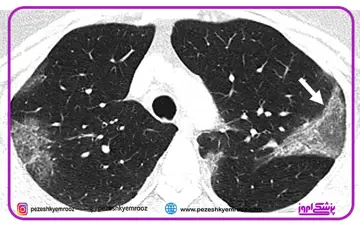

ارزش تصویر برداری پزشکی در تشخیص و ارزیابی کووید-19

جایگاه تصویر برداری پزشکی در تشخیص درگیری ریوی بیماران کرونایی از ارزش بسیار بالایی برخوردار است .انجام سی‌تی‌اسکن ریه بدون تزریق کنتراست روش پیشنهادی در تشخیص و همچنین ارزیابی بیمار حین درمان خواهد بود .